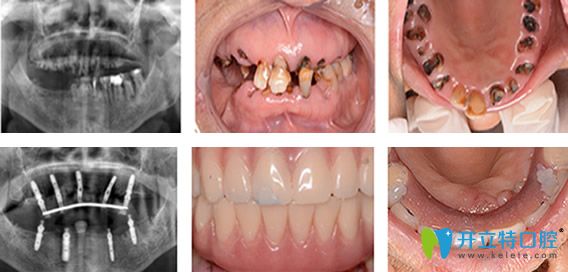

1950后 / 程阿姨

職業(yè):單位退休職工       癥狀:全口牙缺失

需求:種一口好牙檢查與診斷:牙槽骨缺損嚴重

種植方案:牙槽骨骨量修復(fù),德國ICX全口種植

主診醫(yī)生:劉旭光

種植牙過程及結(jié)果展示:

70歲老太在珠江口腔種植牙過程及結(jié)果展示